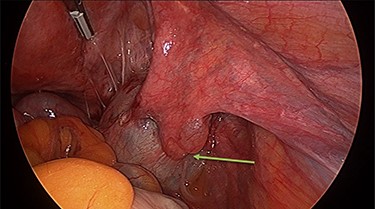

Operation findings consisted of left hydrosalpinx and para-tubal cyst adhered to pouch of douglas, with the left tube torted 3 times (Figs 4 and 5). There was a 5-cm para-tubal cyst on the right tube adhered to right side of pelvis/rectum/pouch of douglas (Fig. 6). The ovaries appeared normal.

Right para-tubal cyst, implanted to the pouch of Douglas and right ovarian fossa.

Diagnostic laparoscopy is the only method of confirming tubal torsion [6]. Surgical technique for correcting isolated tubal torsion may include conservative (detorsion) or definitive management (salpingectomy). Choice of management will be influenced by patient factors including age, completion of fertility and symptoms, as well as surgical factors including ease of detorsion, appearance of revascularization and associated pelvic pathology. Because isolated tubal torsion is difficult to distinguish clinically from differential diagnoses, delay in surgical exploration often leads to necrotic appearances of the tube, requiring salpingectomy [5].